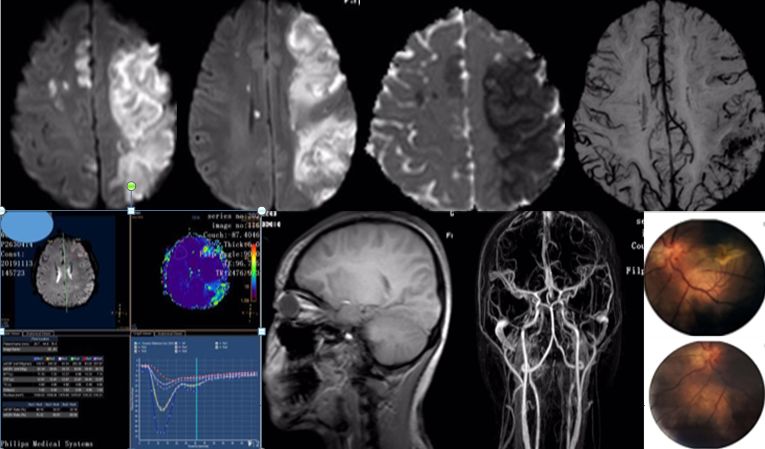

患者,21岁女性,患者3小时前做某手术后突 发右侧肢体乏力、意识不清。

发病24小时磁共振:

答案:脑型脂肪栓塞综合征。患者做了自体脂肪填充术。脂肪栓塞综合征(fat embolism syndrom,FES)是指直径为10~40μm的血管内脂肪颗粒阻塞血管腔而引起的一系列病理生理改变的临床综合征。FES常发生于骨创伤及骨手术病人。FES潜伏期为6~24h,FES 的典型三联征为低氧血症、意识障碍和瘀斑。

女,36岁,突发意识障碍伴抽搐。

答案:狼疮脑病合并可逆性后部白质脑病综合征(PRES)。补充病史:SLE病史。患者青年女性,有SLE病史,发作性神经系统症状,结合影像学考虑PRES。轻度PRES表现为皮质下或皮质下白质水肿,无实质出血、占位效应、或仅累及脑干或基底节中的一个。中度PRES表现为融合性水肿,从皮质向深部白质延伸,但不延伸至脑室边缘,小脑、脑干或基底节区中有两个轻度受累。重度PRES表现为从皮层到脑室的融合性水肿,或水肿或出血引起中线移位,小脑、脑干或基底节区均受累。

PRES本质上是一种可逆性的血管源性水肿,伴急性神经系统症状,如癫痫发作,脑病,头痛,视觉障碍等。常见原因为:高血压、肾衰竭、使用细胞毒*药性**物、自身免疫性疾病、子痫前期或子痫。约半数PRES患者既往有自身免疫性疾病,如:SLE、血栓性血小板减少性紫癜、甲减、硬皮病、Crohn病、溃疡性结肠炎、类风湿性关节炎、干燥综合征、结节性多动脉炎、肉芽肿性血管炎和视神经血管炎。PRES常由急剧的血压波动或细胞因子对血管壁的直接作用致内皮损伤,引起血脑屏障的破坏,继而引起脑水肿。对称性枕叶皮质下病变要和MELAS鉴别,二者形似神也似。MELAS 的MRI 表现为后部皮层信号改变、脑萎缩、基底节信号改变和钙化、脑白质营养不良。急性期通常会出现 T2 和 FLAIR 高信号,DWI 成像弥散受限。